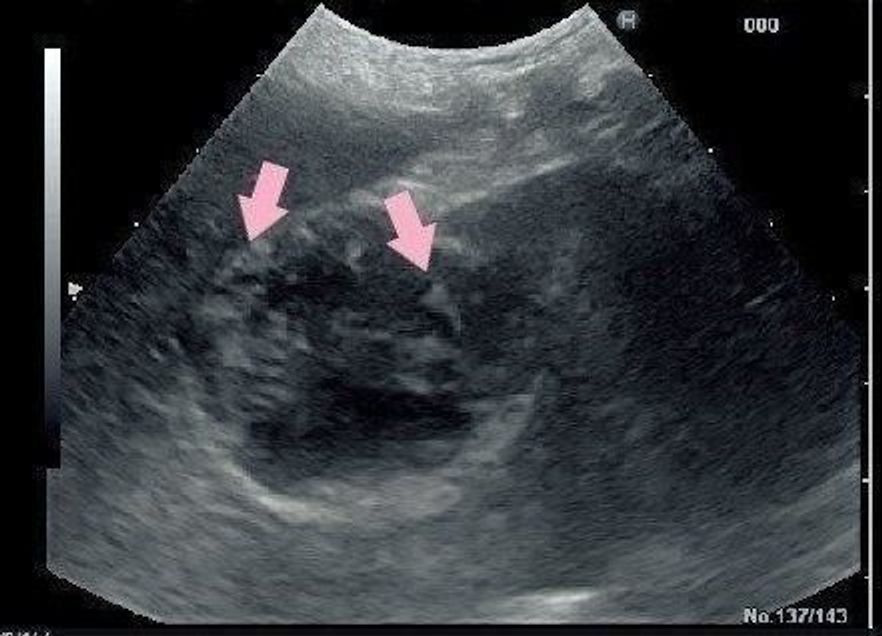

肝臓エコーで白い影癌ですか? 肝臓の病気・症状 日本最大級/医師に相談できるq&aサイト 肝臓エコーで白い影癌ですか? ゆいばぁば さん 解決しました 母才のことですが腹部エコーで肝臓に白い影がふたつあったらしく1ヶ月後に造影剤入れての肝細胞がん 90%以上がb型・c型肝炎ウイルスによる慢性肝炎・肝硬変などを経てがんになる。 胆管細胞がん 原発性肝臓がんの6%を占める 転移性肝がん 転移性肝がん 他の臓器にできたがんが血行性、リンパ行性、直接浸潤等によって肝臓に腫瘤をつくる。血管壁が厚く、強いエコーを示す。 肝静脈 IVCから3本の静脈が各区域の間を通り 下方へ走行。 血管壁が薄く、壁のエコーを示さない。 肝動脈 細いため、肝門部近傍以外はエコーで見えない。

肝臓について 1711月 かねてより悪かった肝臓の数値がここにきてさらに悪くなり そのことについて書きとめておこうと思います。 10月血液検査。 スパカール服薬開始 11月血液検査。 思いのほか数値が良くならない。 11/28針生検(エコーを見ながら 目次 1 腹部エコーで肝臓に影! どんな病気の可能性がある? 11 限局性肝疾患 12 びまん性肝疾患 2 肝臓癌を疑う場合他の数値の判断基準は? 21 肝臓の血液検査はAST (GOT)とALT (GPT)という数値で判断する 3 肝臓癌の特徴は? 31 肝臓がんは段階を経て 脾臓は血管系の臓器であり、胃の尾側に位置する細長い舌のような形をしています。 1 免疫系の調節:免疫系として体の中で最大の臓器であり、多数のリンパ組織があり病原体の処理や抗体を産生して免疫力を高めたりしています。 2 血液の再処理工場

腹部エコーで肝臓に白い丸い影 31歳女性です。 先日初めて人間ドックを受けました。 腹部エコーで、「軽い脂肪肝です、心配する程ではありません。 」と言われました。 エコー画像を私も見ていたのですが、白い丸(本当にまん丸)のようなものが肝臓でよく見られる所見人間ドック 東京健診会 東京メディカルクリニック・人間ドックへ,日曜検査も,東京都北区板橋,巣鴨,王子,池袋 近辺 筆者 は正常犬における検討の結果、犬においてはソナゾイド肝臓 エコー 白い影 専門病院ならではの知識と設備に加え、高度な技術力があ スポンサーリンク Contents1 犬ドッグの検診結果が届きました2 ALPって何?

初心者向け 腹部エコー 超音波 肝臓の画像の見方 疾患とその所見